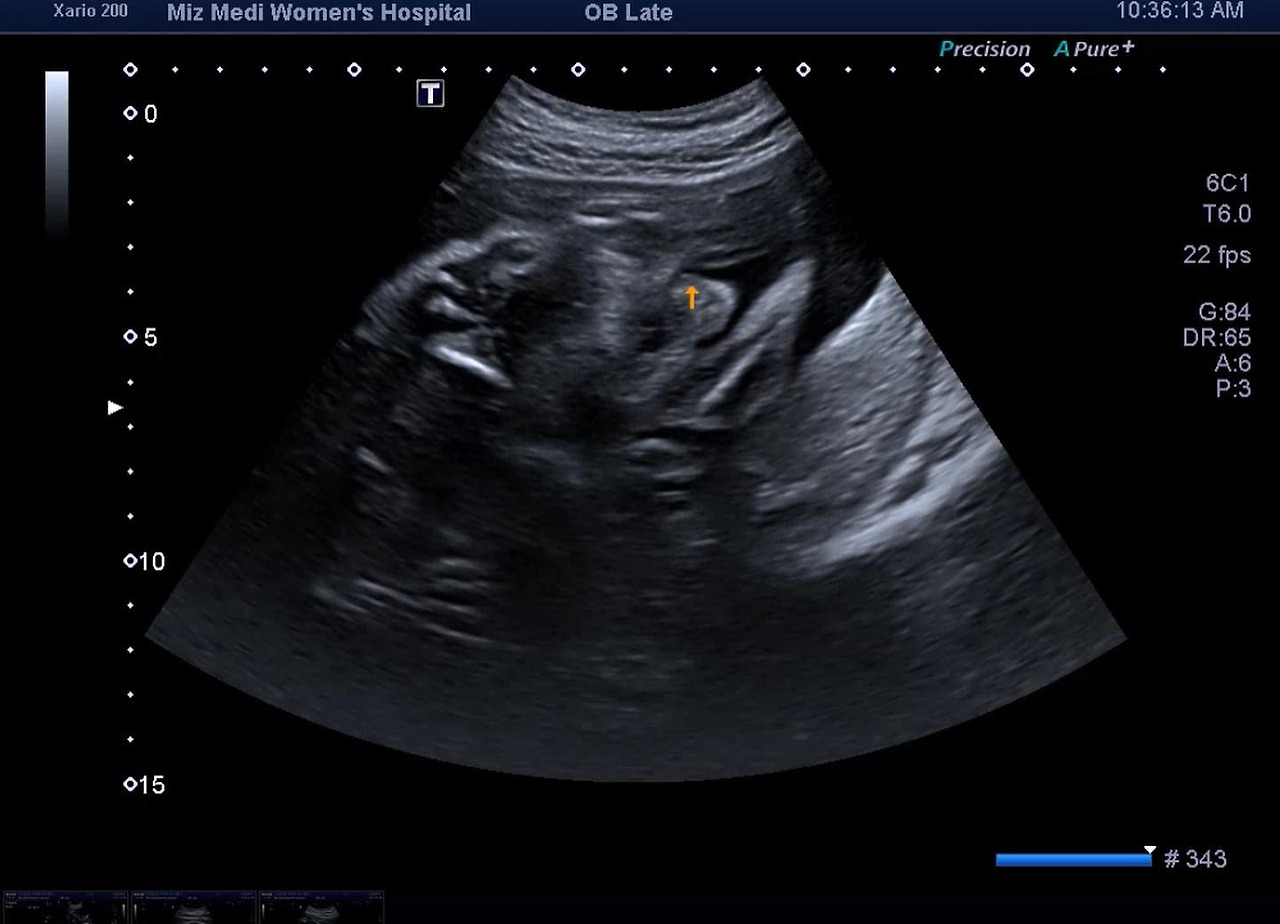

다올이 콧구멍

29주 코.jpg